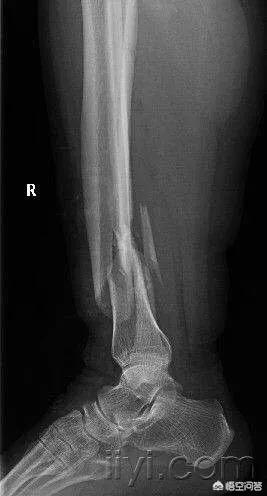

从广义来说的话,就是一个碗摔碎了与摔的粉碎。从医学的角度来说,就是骨的连续性与完整性中断,且骨折块大于3块以上,这就叫粉碎性骨折。

粉碎性骨折肯定比斜行骨折、裂隙性骨折、青枝骨折.....等单程性骨折要严重的多,因为他是高能量损伤,且骨折不稳定,手法复位困难,所以基本上都需要要手术固定治疗。

骨折可以分为很多种类型,而粉碎性骨折是我们所见到的最多的一种骨折。所谓粉碎性骨折是指骨头的完整性以及连续性遭受到破坏,是一种比较严重的骨折。

骨折是各种原因导致的骨皮质的连续性和完整性中断,而粉碎性骨折就属于完全性骨折,是指骨质碎裂成三块以上。粉碎性骨折是非常严重的骨折,手术难度比较大。如果治疗不及时,手术不恰当容易遗留下问题。粉碎性骨折后遗症通常有以下几种情况:

粉碎性骨折,听起来貌似很严重的样子。其实也没有大家想象的碎成了渣渣那种样子。 只是从定义上来讲就是骨折后骨块大于等于3块以上统称为粉碎性骨折。